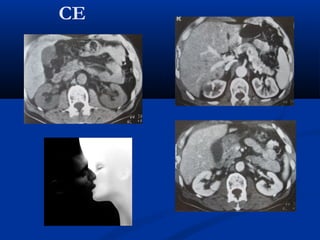

CE

U maùu vuønghaømU maùu vuøng haøm (T)/(T)/ Daõn tónh maïchDaõn tónh maïch caûnh ngoaøi (T)caûnh ngoaøi (T)